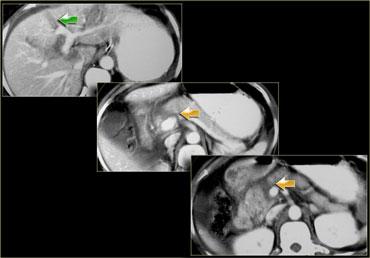

Trước tiên hãy quan sát các hình ảnh bên trái của bệnh nhân bị chấn thương gan.

Mô tả các dấu hiệu hình ảnh.

Sau đó tiếp tục.

Các dấu hiệu bao gồm:

- Mũi tên xanh lá: vùng giảm tỷ trọng hình bầu dục phù hợp với tụ máu

-

Mũi tên vàng: vùng giảm tỷ trọng hình tuyến tính phù hợp với đường rách.

Lưu ý rằng đường rách này đi qua nhánh trái của tĩnh mạch cửa - Mũi tên xanh dương: vùng giảm tỷ trọng mờ, ranh giới không rõ phù hợp với dập gan

- Dịch quanh gan

- Gần như có sự đứt ngang hoàn toàn của gan, nhưng cả hai thùy đều còn ngấm thuốc, cho thấy nguồn cung cấp mạch máu vẫn còn bình thường.